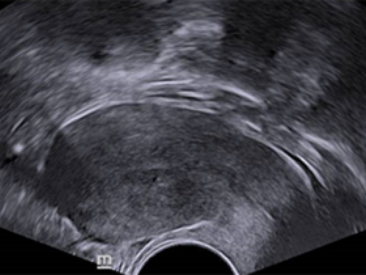

ImĂĄgenes clĂnicas